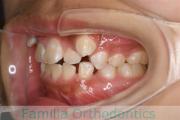

No.16V-202

- 主な症状:

- 叢生

- 年齢:

- 10歳

- 性別:

- 男性

- 抜歯部位

- 上:

- 44

- 下:

- 4|3

- 主な使用装置:

- FEA

- 治療にかかった費用:

- 92万円

歯並びを治したいということで小学生のときに来院されました。二期治療で小臼歯抜歯の可能性が高いと判断しましたが、スペースの不足が著しいため、上下を拡大してから成長観察に移行しました。

左下犬歯に異常があったので、この歯と左右上&右下の小臼歯を抜歯してマルチブラケットを行いました。約4年、30回以上の通院が必要でした。